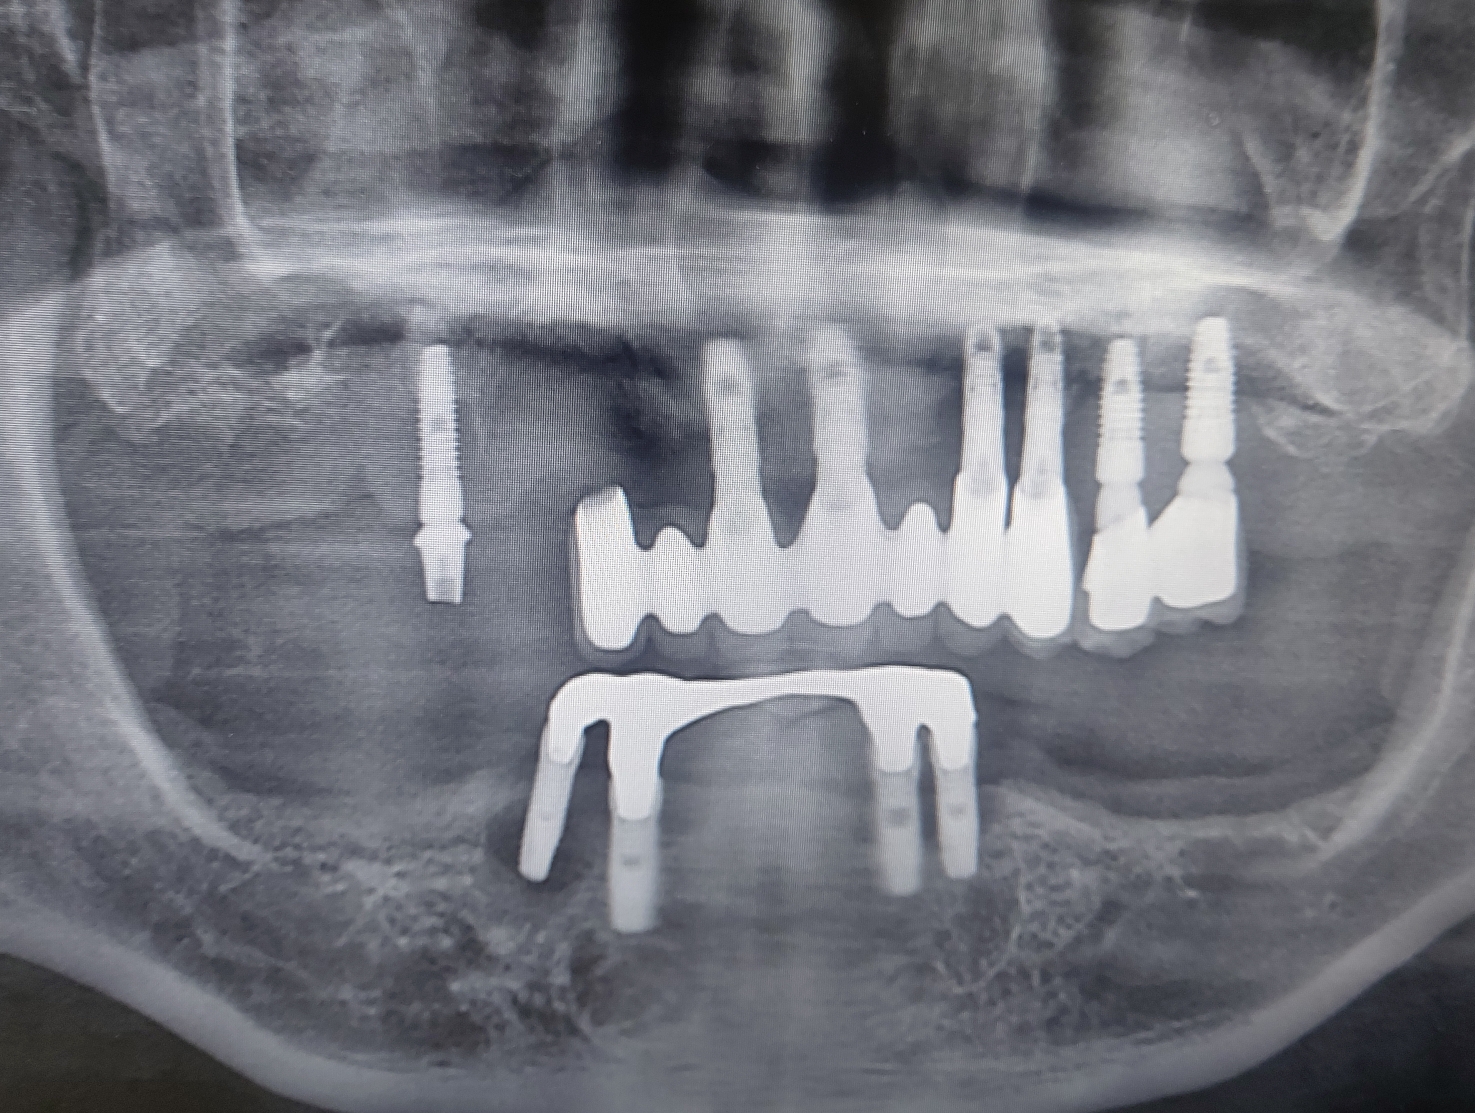

2008년도경에 치료했던 임플란트가 이젠 사용할 수 없게 되어서 내원한 환자분이었습니다.

내원시 상 하악 임플란트는 심각한 골흡수 양상을 보였고 일부는 골유착이 깨져서 탈락한 상태였습니다.

치료계획은 상하악 임플란트 모두 제거하고

♧ 상악은 다시 양쪽 상악동 거상술시행후 지연식립

♧ 하악은 아래 임플란트 제거후 즉시 부하